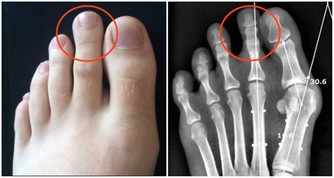

當我們上廁所看書或者看手機時,注意力會被分散,即使有便意衝動,大腦也可能會“忘了”。大便的時間越長,一方面會形成痔瘡,另一方面會致使大便乾結,發生便秘。